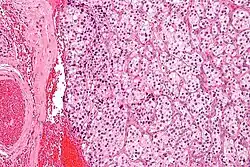

| Micrograph of a carotid body tumor (a type of paraganglioma) | |

On microscopic inspection, the tumor cells are readily recognized. Individual tumor cells are polygonal to oval and are arranged in distinctive cell balls, called Zellballen.[9] These cell balls are separated by fibrovascular stroma and surrounded by sustentacular cells.

By light microscopy, the differential diagnosis includes related neuroendocrine tumors, such as carcinoid tumor, neuroendocrine carcinoma, and medullary carcinoma of the thyroid.

With immunohistochemistry, the chief cells located in the cell balls are positive for chromogranin, synaptophysin, neuron specific enolase, serotonin, neurofilament and Neural cell adhesion molecule; they are S-100 protein negative. The sustentacular cells are S-100 positive and focally positive for glial fibrillary acidic protein. By histochemistry, the paraganglioma cells are argyrophilic, periodic acid Schiff negative, mucicarmine negative, and argentaffin negative.